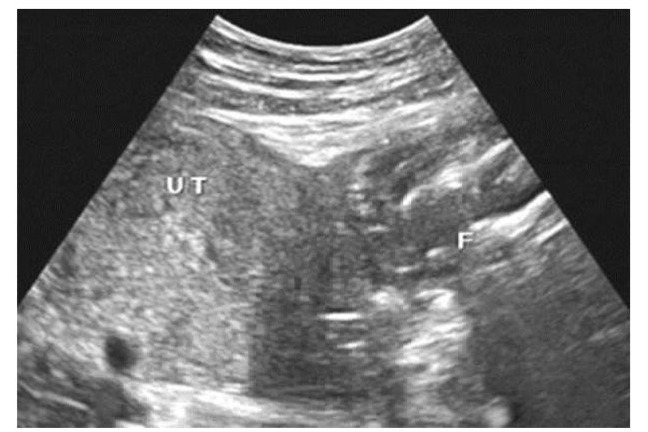

The patient, who has a four-year-old son from her previous pregnancy, was sent for a repeat obstetric ultrasound scan which showed an empty uterine cavity and the apparently dead foetus thrown to the left side of the uterus in the abdominal cavity.